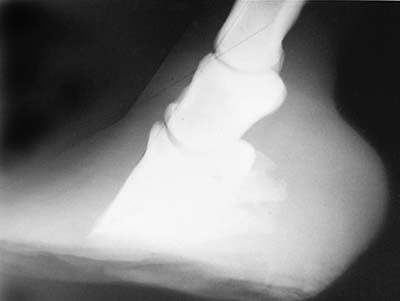

BEFORE. A chronic foundered hoof before the wall is unloaded.